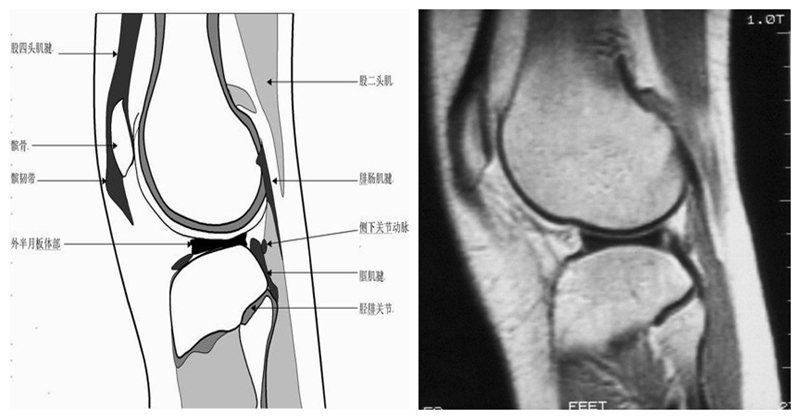

矢状位解剖第三层

矢状位解剖第四层